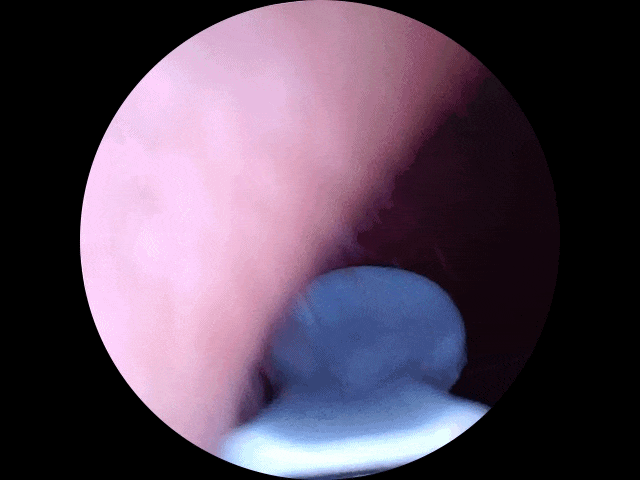

Step 2:耳道探险实录

●第一次把耳勺伸进耳朵时,我仿佛打开了新世界:震撼画面:屏幕上赫然出现一片“金色沙漠”(耳垢)+“黑色灌木丛”(耳毛),甚至能看到耳膜若隐若现(友情提示:别戳它!)。

●精准打击:用耳勺头轻轻一刮,耳垢像雪崩一样哗啦啦掉下来;顽固分子换金属镊子一夹,爽感堪比挤黑头。